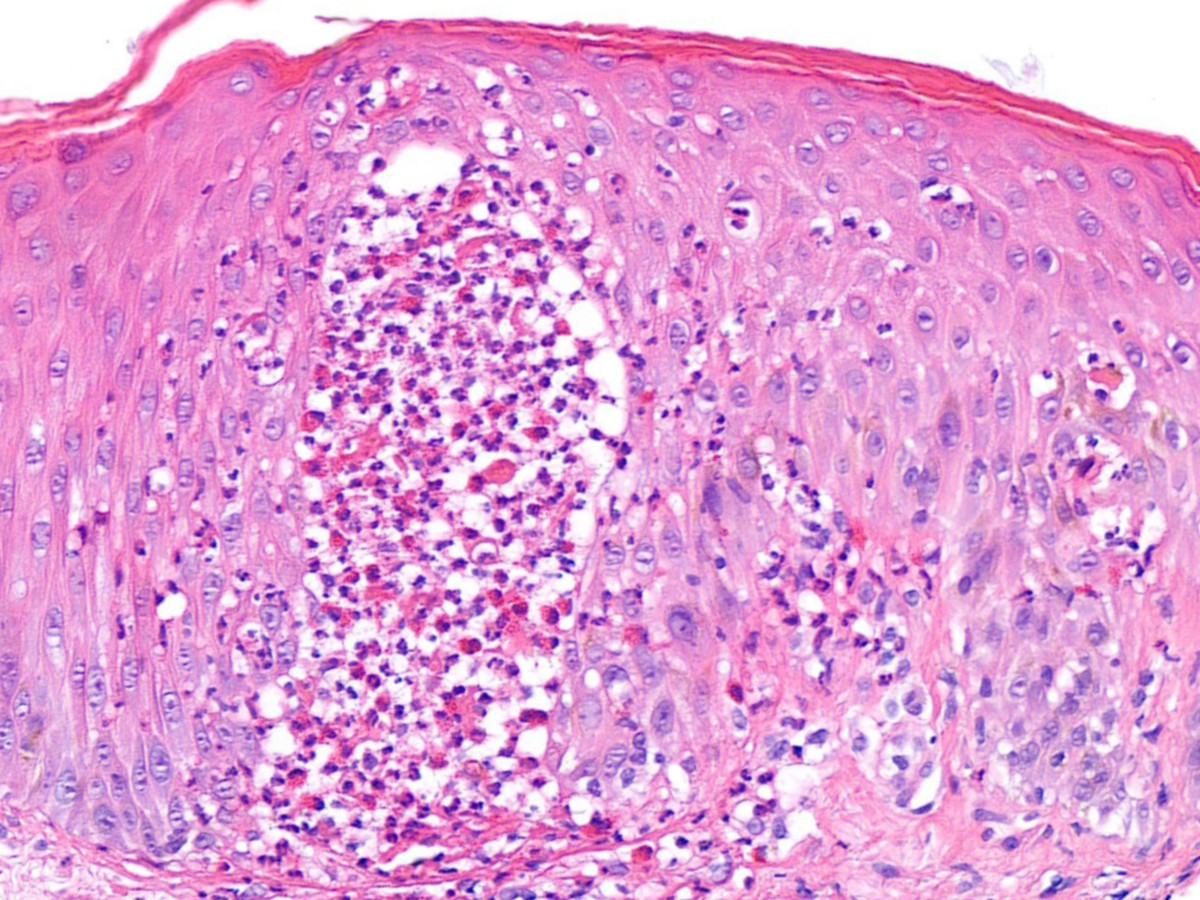

Histologie AGEP:

Subcorneale of intraepidermale spongiforme pustel, oedeem van de papillaire dermis, soms milde vasculitis, infiltraat van leukocyten en eosinofielen, en/of focale necrose van keratinocyten. De pustels zitten meestal hoog in de epidermis, zijn groot en bevatten eosinofielen.

Histologie AGEP, acute gegeneraliseerde exanthemateuze pustulosis Histologie AGEP, acute gegeneraliseerde exanthemateuze pustulosis Histologie AGEP, acute gegeneraliseerde exanthemateuze pustulosis

PA AGEP PA AGEP PA AGEP

PA-foto's: dr. S. Roshani, Afdeling Pathologie, Dermatologie AMC